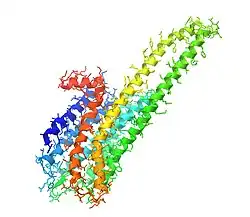

The 5-HT2A receptor is a member of the class A (rhodopsin-like) G protein-coupled receptor (GPCR) family, characterized by seven transmembrane α-helices connected by extracellular and intracellular loops.[47][48] Its ligand-binding pocket is composed of two adjacent subpockets: the orthosteric binding pocket (OBP) and an extended binding pocket (EBP), with a unique side-extended cavity near the orthosteric site that distinguishes it from related receptors.[49][50] Ligands are anchored primarily through a conserved aspartate residue (D155^3.32) that interacts with their charged amine groups, while additional interactions involve hydrophobic contacts and hydrogen bonds with residues in both the OBP and EBP.[50][51] Structural studies reveal that the receptor undergoes significant conformational changes upon activation, particularly in transmembrane helices 3 and 6, which facilitate G protein coupling and signal transduction.[47][50] The extracellular ligand-binding pocket is closed by a flexible “lid,” and the intracellular region includes a short helix (H8) stabilized by π-stacking interactions, both of which contribute to the receptor's dynamic conformational landscape.[50] These structural features underlie the receptor's ability to recognize diverse ligands and mediate complex signaling behaviors.

The cryo-EM structures of the serotonin 5-HT2A receptor with a variety of serotonin 5-HT2A receptor agonists, including the tryptamines serotonin (neurotransmitter and endogenous agonist), psilocin (psychedelic), and dimethyltryptamine (DMT) (psychedelic), the lysergamides LSD (psychedelic) and 2-bromo-LSD (BOL-148) (non-hallucinogenic), and the phenethylamines mescaline (psychedelic) and RS130-180 (β-arrestin-biased agonist with unknown hallucinogenic potential), have been solved and published by Bryan Roth and colleagues.[52][53]